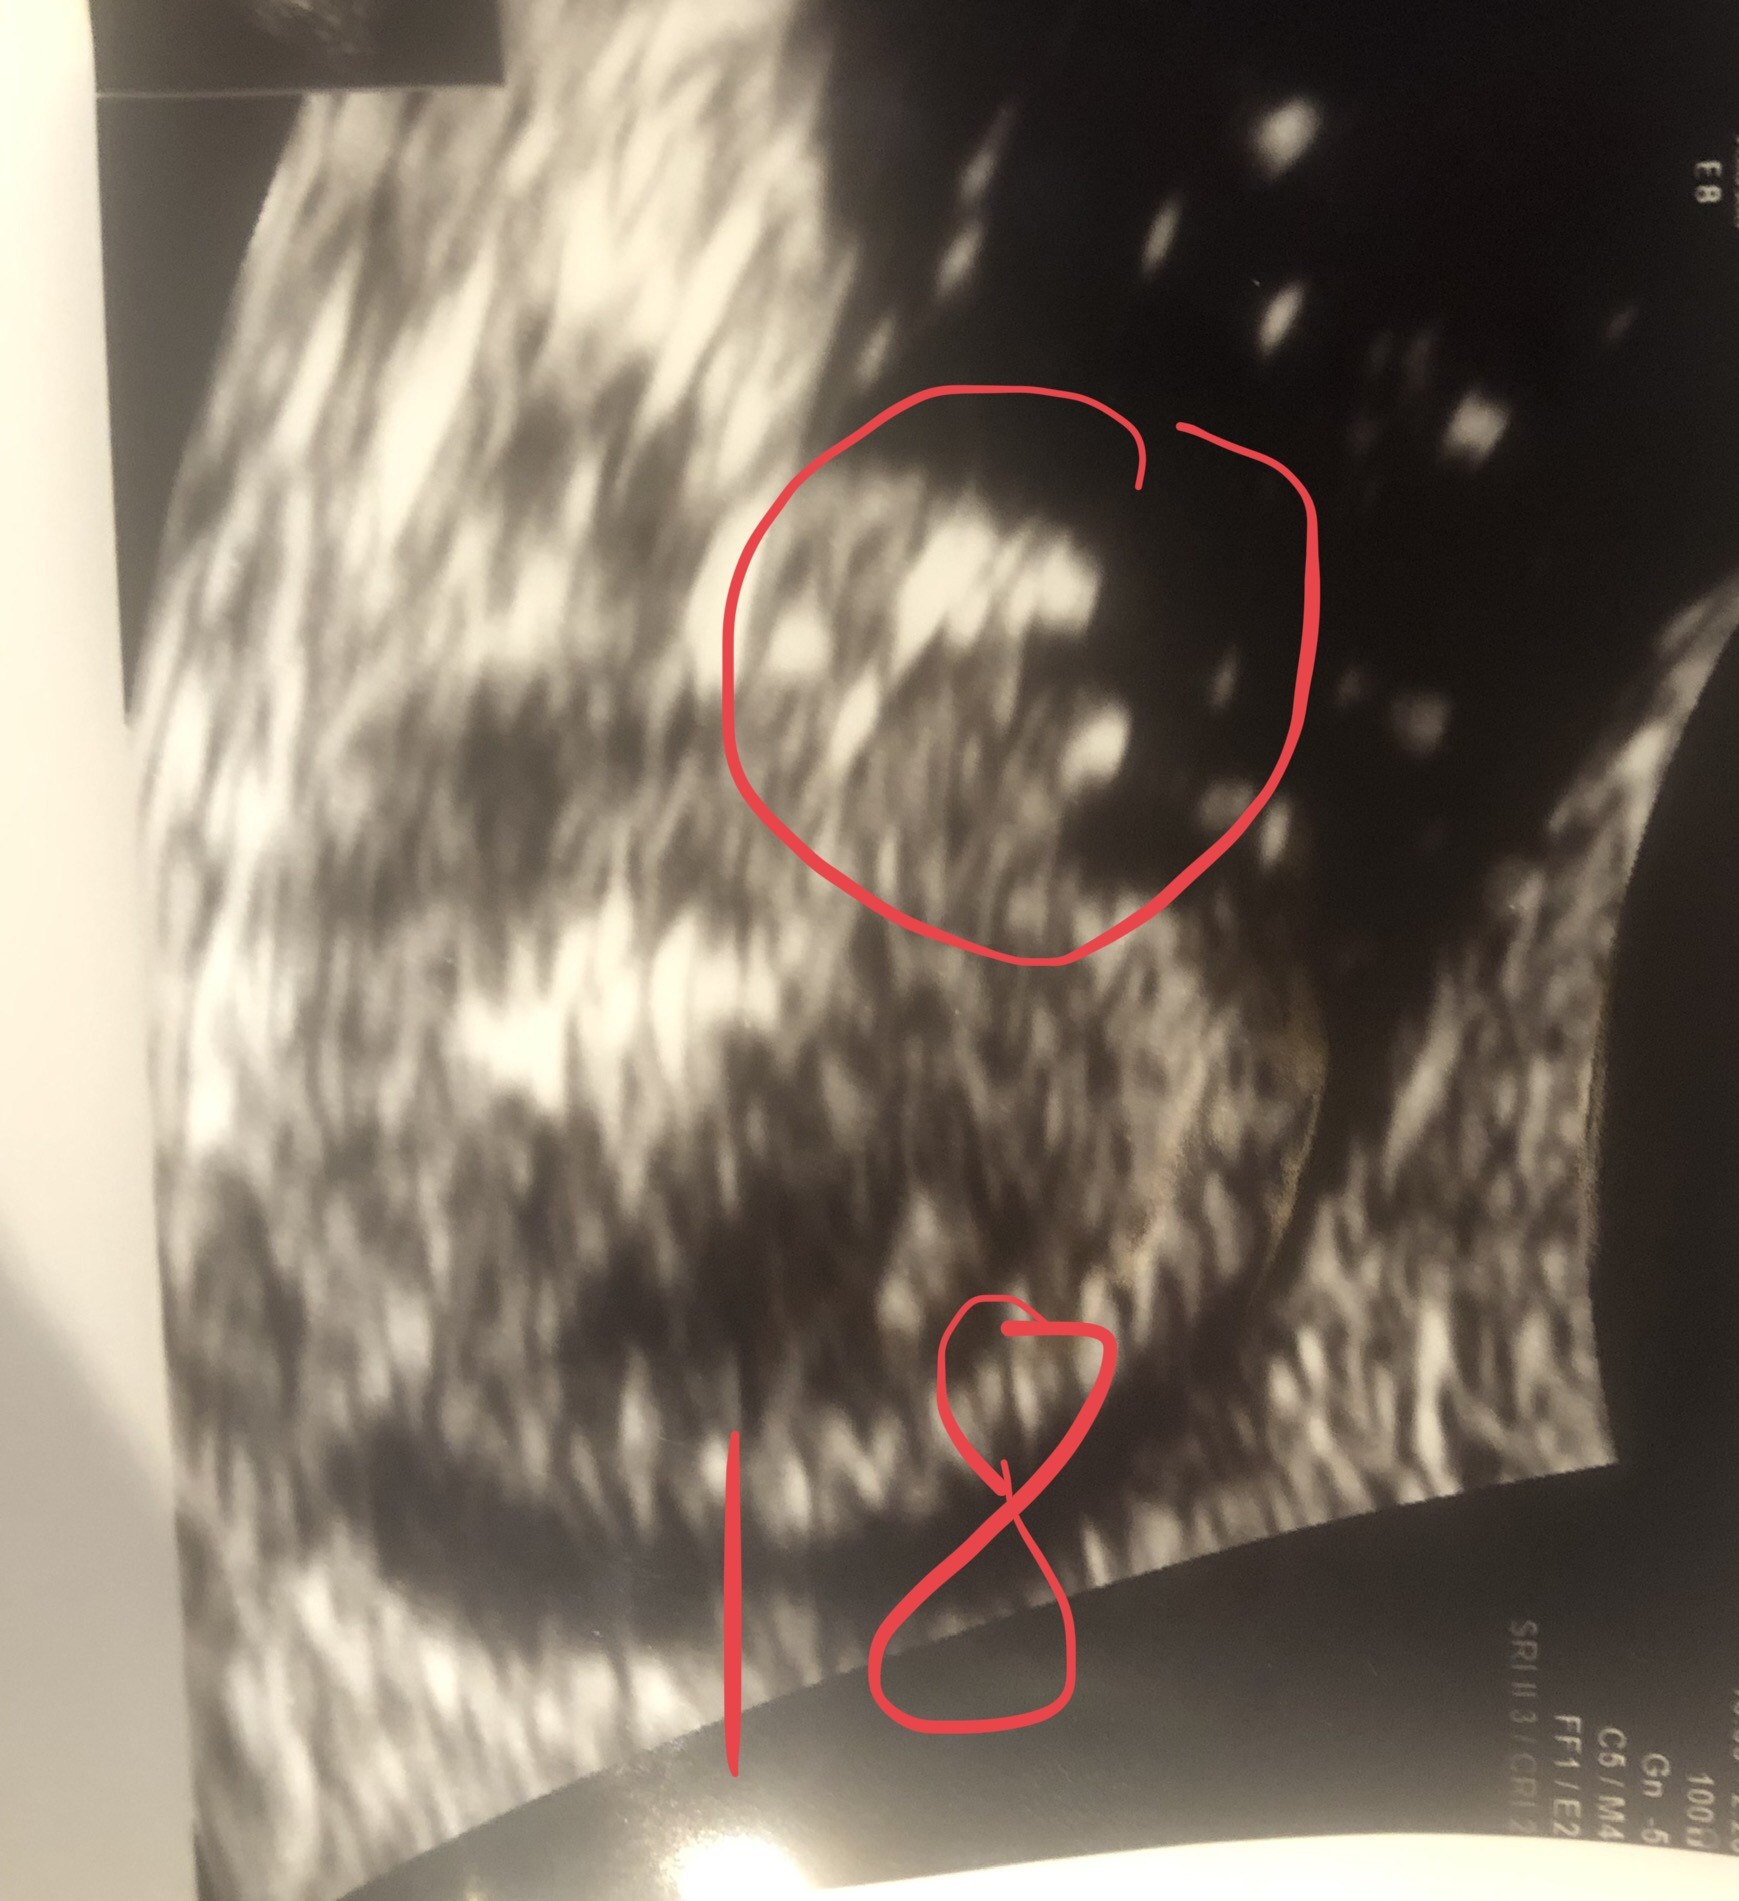

Witam w 19 tygodniu ciąży dowiedziałam się ze będę miała dziewczynkę w 20 tyg okazało się jednak , że to chłopak. Sama już nie wiem bo na jednym usg widać na pewno dziewuche a na drugim chłopca. Może to pempowina ?? Może ktoś mi pomoże rozwiązać ta zagadkę